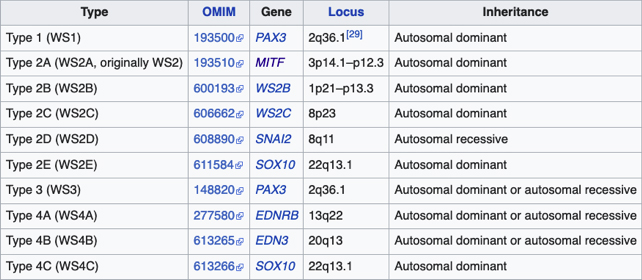

Síndrome de Waardenburg (Bilateral) PAX3 (Neurocristopatia) (22,23)Es un grupo con unas condiciones genéticas raras por lo general de herencia autosomica dominante, es una forma de albinismo irregular, fluctuante; tienen epitelio pigmentario normal y visión normal; sinembargo en el tipo II y IV hay también herencia autosomica recesiva.- Se describen 4 tipos en este síndrome.

El tipo 1 se caracteriza por Telecanto, cierto grado de Hipoacusia congénita y deficiencias pigmentarias en piel con manchas blancas, Mechon blanco en el pelo y deficiente pigmentación del Iris bilateral. Mutación del PAX3

El tipo 2: es el mas frecuente siendo raro, Pueden tener mechón blanco en el cuero cabelludo, manchas blancas en la piel y heterocromia del iris por hipopigmentación bilateral. Mutación del MITF( factor de transcripción asociado a microoftalmia). Aquí se describe también, el Síndrome de Tietz,(descrito en 1963 por Walter Tietz) semejante al tipo 2 con Hipoacusia neurosensorial e Hipopigmentación generalizada de la piel a diferencia de los parches en el Waardenburg. Los ojos tambien son afectados, con Iris claro e hipopigmentación en el epitelio pigmentario de la retina. Autosómico dominante ( Mutación MITF)4

Tipo 3 - Es una mutación más severa del tipo 1, en el cual las manos y brazos también tienen malformaciones: contracturas permanentes y dedos fusionados. Mutación del PAX3

Tipo 4: Tiene enfermedad de de Hirschsprung en el que hay ausencia de inervación intestinal.Mutación del SOX10